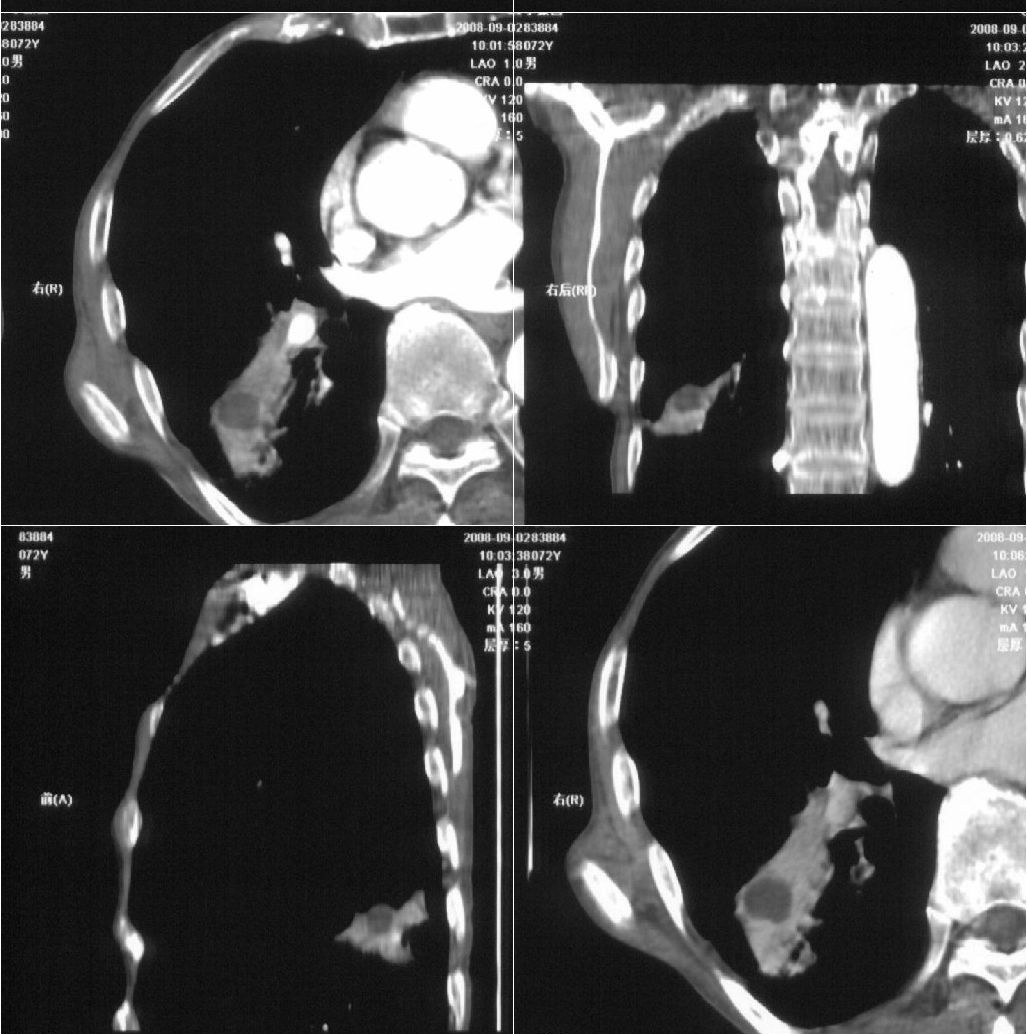

标题: CT15789:男性,72岁。食管癌术后14年。 [打印本页]

标题: CT15789:男性,72岁。食管癌术后14年。

痰培养:见葡萄球菌,霉菌少量生长。(此片系外院所作,仅提供了增强后的ct值为100hu,中心的坏死部分无强化,患者现在身体状况欠佳,为恶液质状态)

注意排外食管支气管瘘引起的肺部感染

考虑右肺下叶感染性病变(肺脓肿?);建议抗炎治疗后复查。

考虑右下肺慢性感染性病变

符合机遇性感染,真菌可能性大。